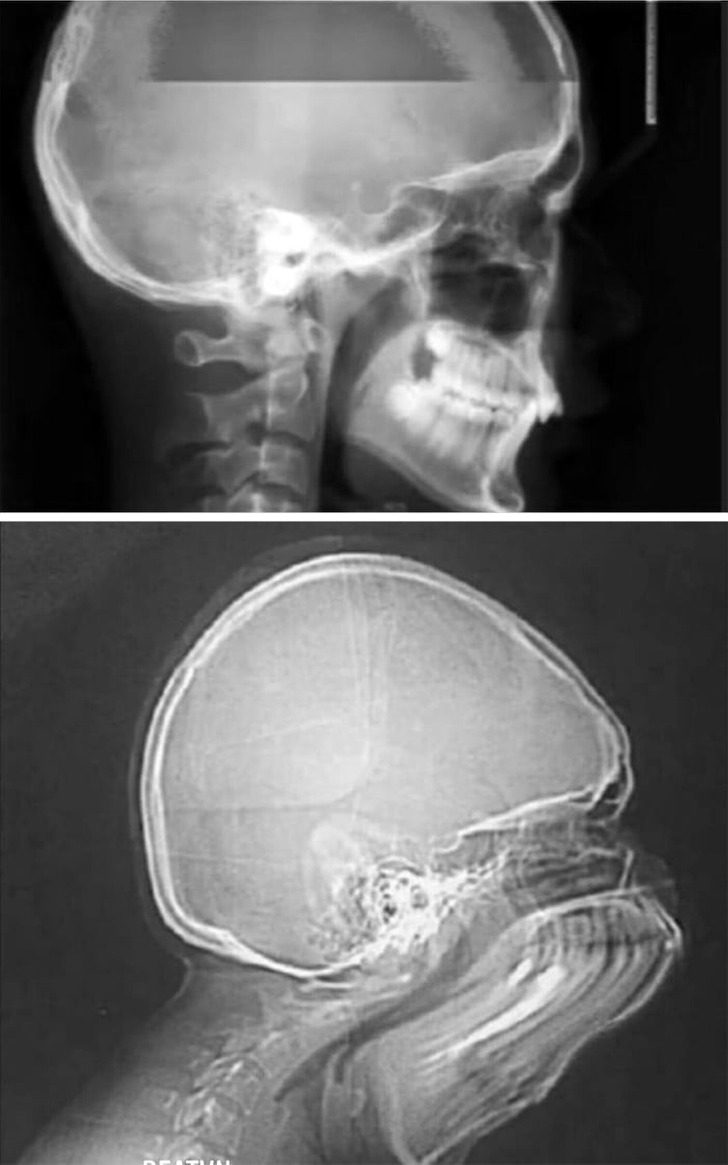

3. «Почему я хожу с бородой? Подбородка потому что нет, сразу шея»

5. Иногда мы можем выглядеть так

6. Или так